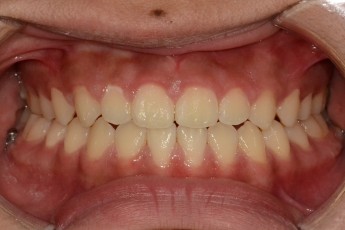

Before

After